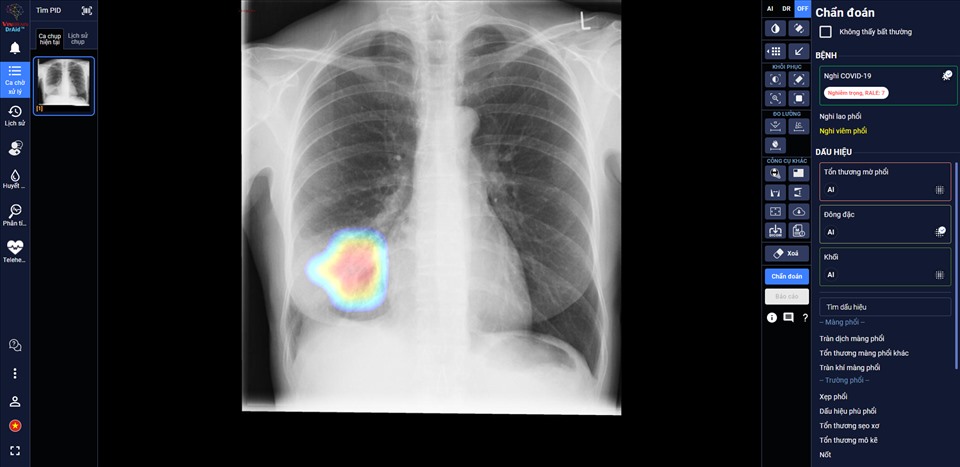

DrAid против COVID-19 – основанный на искусственном интеллекте продукт компании VinBrain корпорации Vingroup – одобрен научным советом Минздрава Вьетнама и рекомендован к ежедневному применению в больницах страны. Этот инструмент может классифицировать и прогнозировать течение болезни у пациентов с коронавирусом, что помогает более эффективно бороться с пандемией.

По словам врачей из Медицинского центра уезда Киань (провинция Хатинь) искусственный интеллект помогает им следить за состоянием больных каждый день, оценивать степень повреждения органов и выявлять труднонаблюдаемые проблемы.

DrAid против COVID-19 является первым в своем роде приложением на основе ИИ, которое рекомендует Минздрав для больниц Вьетнама.